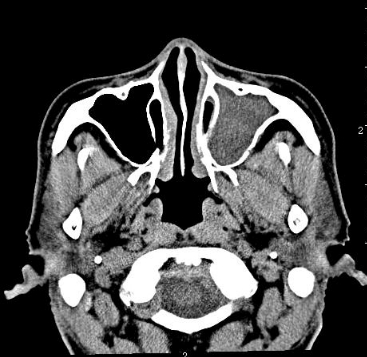

鼻竇CT影像系統是一種高精度的醫學成像技術,專門用于鼻竇區域的詳細檢查。這種系統通過計算機斷層掃描(CT)技術,能夠生成鼻竇區域的高分辨率圖像,幫助醫生準確診斷和評估鼻竇疾病。

高精度鼻竇成像的解決方案包括以下幾個方面:

多平面成像:

水平位:顯示鼻竇的橫向結構,有助于觀察鼻腔和鼻竇的寬度。

冠狀位:顯示鼻竇的前后結構,有助于觀察鼻道竇口復合體和中鼻道的情況。

矢狀位:顯示鼻竇的縱向結構,有助于觀察蝶竇和蝶竇垂直的情況。

三維重建:

通過計算機三維重建技術,可以生成鼻竇區域的三維圖像,幫助醫生更直觀地了解鼻竇的解剖結構和病變情況。

高分辨率掃描:

使用高分辨率的CT掃描儀,可以捕捉到更細微的解剖結構和病變,提高診斷的準確性。

低劑量輻射:

現代CT掃描儀通常采用低劑量輻射技術,減少患者在接受檢查時的輻射暴露,提高安全性。

圖像后處理:

利用先進的圖像處理軟件,可以對CT圖像進行進一步的處理和分析,如測量病變的大小、位置和形狀,幫助醫生制定更精確的治療方案。

快速掃描:

現代CT掃描儀通常具有快速掃描功能,可以在短時間內完成鼻竇區域的掃描,減少患者的不適感和運動偽影的影響。

應用范圍:

鼻竇炎:檢測鼻竇的炎癥程度和位置,幫助醫生制定治療計劃。

鼻息肉:檢測鼻息肉的大小、位置和形狀,幫助醫生確定最佳的治療方案。

鼻竇腫瘤:檢測腫瘤的大小、位置和形狀,幫助醫生制定手術方案。

鼻竇損傷:檢測骨折的位置和程度,幫助醫生制定最佳的治療方案。

鼻竇畸形:檢測鼻竇是否存在畸形,能夠及時發現異常問題。

總之,鼻竇CT影像系統通過高精度的成像技術,為醫生提供了詳細的鼻竇解剖和病變信息,是診斷和治療鼻竇疾病的重要工具。